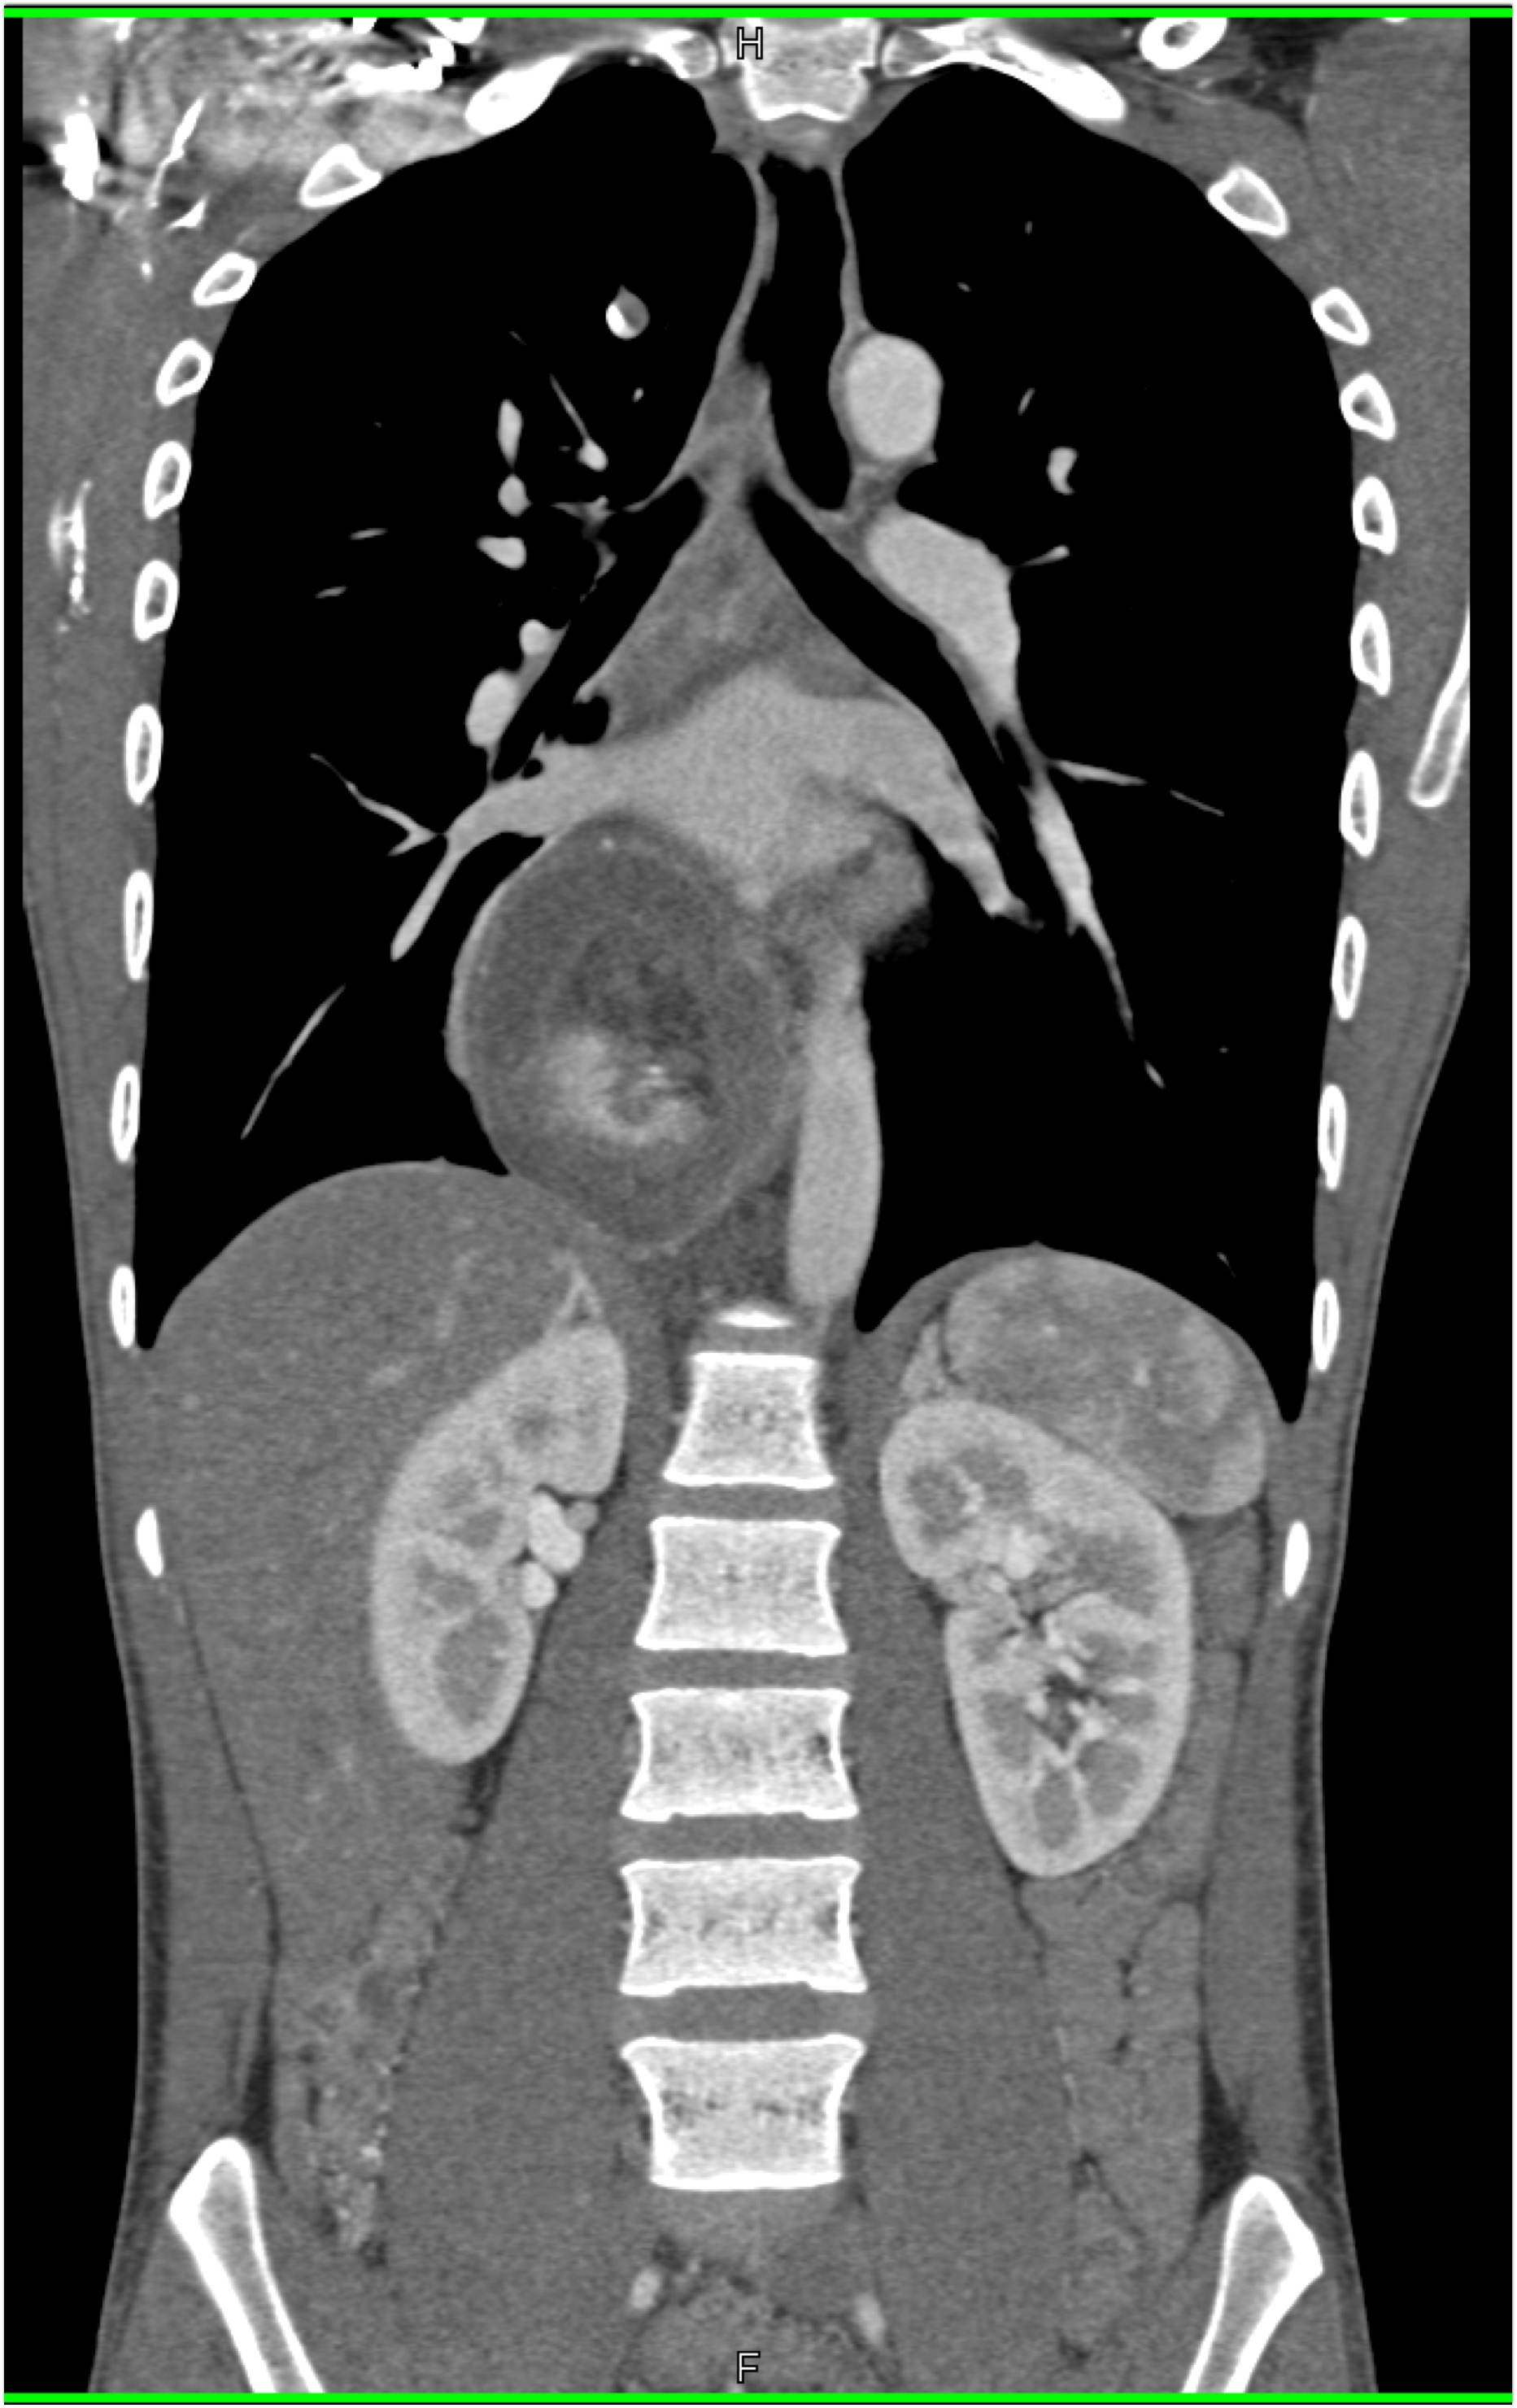

In this patient with suspected GI bleed the most likely diagnosis is?

hiatal hernia

esophagitis

esophageal cancer

achalasia